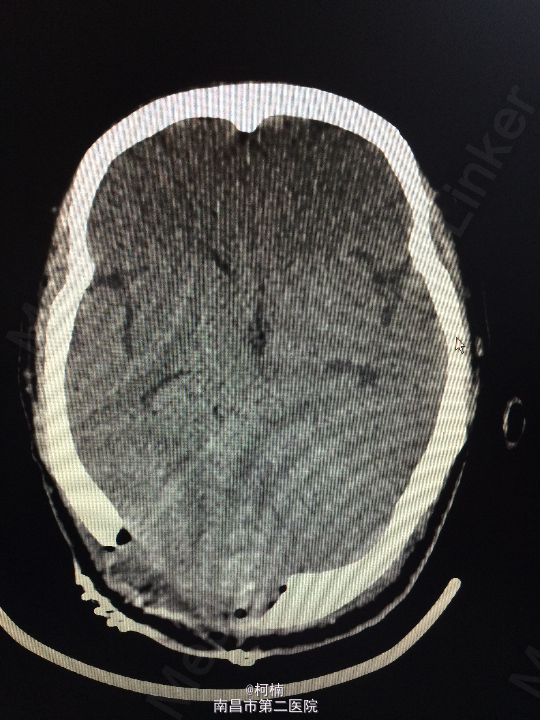

查体:神经系统体查未见明显异常 辅助检查:头颅MR提示右侧桥小脑区占位性病变,考虑脑膜瘤。四脑室狭窄,变形,幕上脑室积水,小脑扁桃体疝